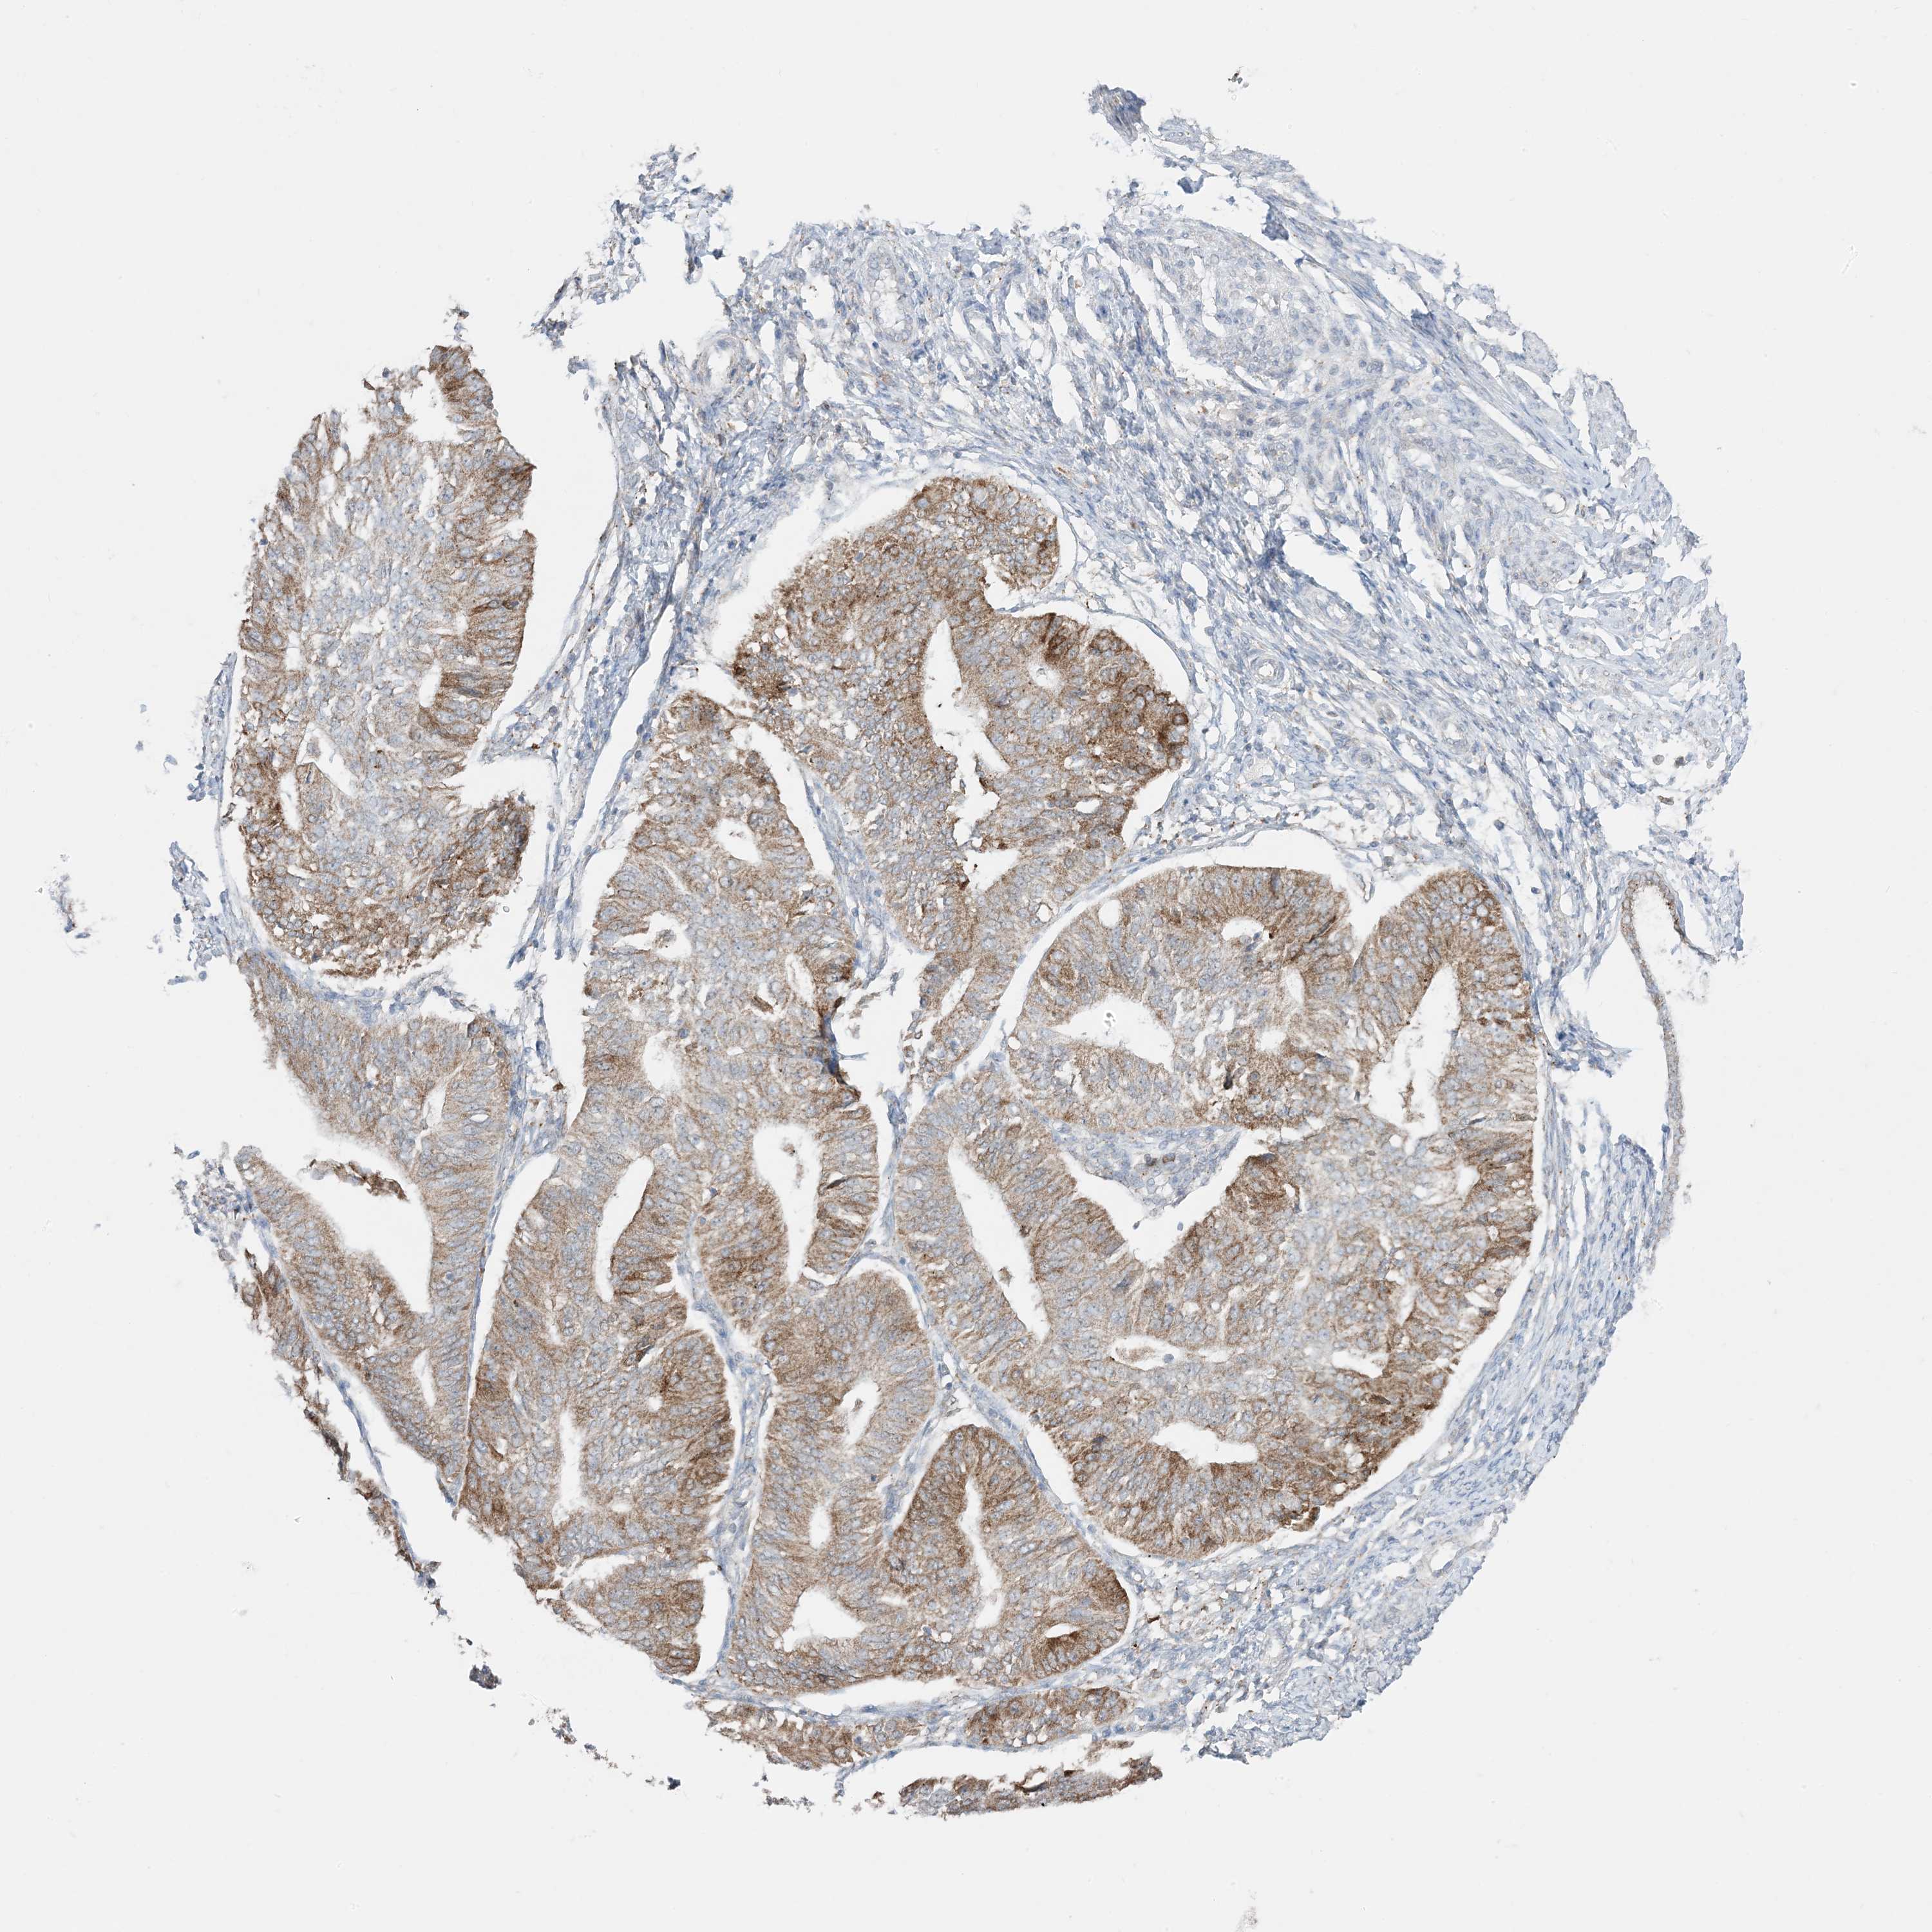

ENDOMETRIAL CANCER - Protein expressioni

A mouse-over function shows sample information and annotation data. Click on an image to view it in a full screen mode. Samples can be filtered based on level of antibody staining by selecting one or several of the following categories: high, medium, low and not detected. The assay and annotation is described here.

Note that samples used for immunohistochemistry by the Human Protein Atlas do not correspond to samples in the TCGA dataset.

Antibody stainingi

Antibody staining in the annotated cell types in the current human tissue is reported as not detected, low, medium, or high, based on conventional immunohistochemistry profiling in selected tissues. This score is based on the combination of the staining intensity and fraction of stained cells.

Each image is clickable and will lead to virtual microscopy that enables deeper exploration of all samples and also displays staining intensity scores, fraction scores and subcellular localization as well as patient and tissue information for each sample.

Antibody HPA001536

Antibody CAB035996

Staining

High

Medium

Low

Not detected

Intensity

Strong

Moderate

Weak

Negative

Quantity

>75%

75%-25%

<25%

None

Location

Nuclear

Cytoplasmic/membranous

Cytoplasmic/membranous,nuclear

Adenocarcinoma, NOS

Neoplasm, malignant, NOS

Adenocarcinoma, metastatic, NOS